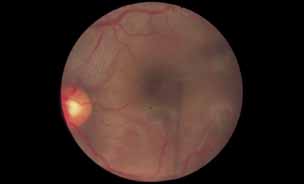

Fig. 6 Presumed ocular histoplasmosis. This patient developed decreased vision with mild vitritis. Color photograph shows a hazy view of the central macula.

Fig. 7 Presumed ocular histoplasmosis. Fluorescein angiogram of Figure 6 demonstrates cystoid macular edema as the cause of this patient's decreased vision.